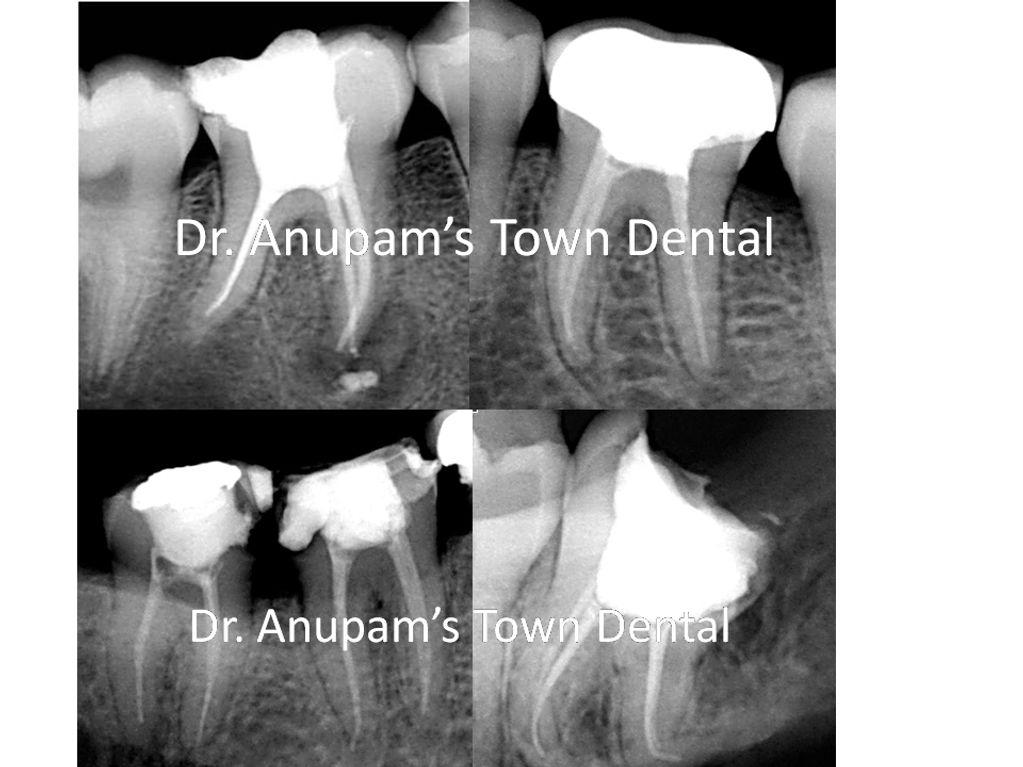

These are the cases of Root Canal Treatment done in our centre.